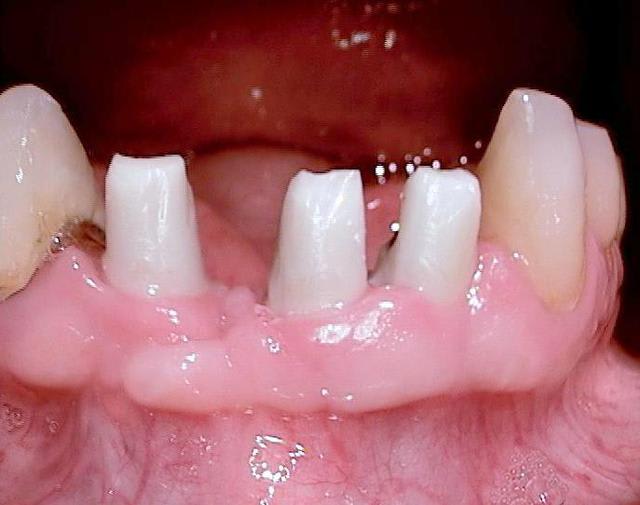

Sur la photo 14 (implants mandibulaires)

Quelle est la longueur des implants ?

J'aime bien ce cas, sauf peut-être pour une certaine proximité des implants, car même si l'os peux être ok, pas facile pour la prothèse et son entretient.

Bonjour, merci pour ta question:

46 : 10mm de longueur et 4,5mm de diamètre (parce que je n ai pas atteint la stabilité primaire avec le condenseur 3,0 la mesure 30Ncm)

45 et 36: 10mm de longueur et 3,5mm de diamètre

44, 42, 31 et 34 : 22 mm de longueur et 3,5 mm de diamètre

32 : 20 mm de longueur et 3,5 mm de diamètre

ton commentaire m a fait remarqué que je n´ ai pas mis la photo de la prothèse du cas! merci ! :-)

ci dessous

cordialement